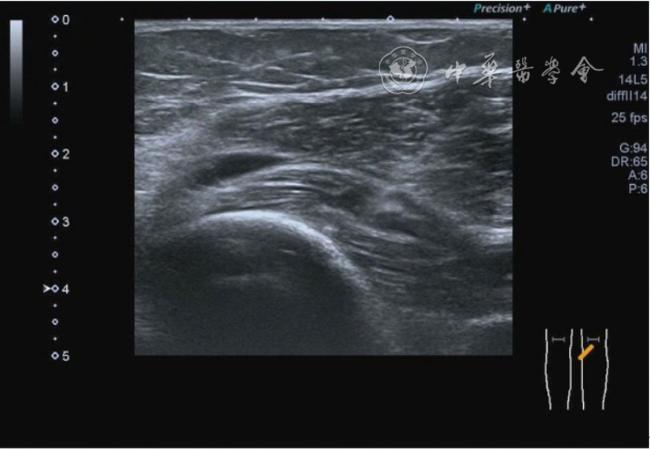

2.膝关节静态结构治疗。动力平衡失调后,继发静态结构变化,出现内外侧副韧带、交叉韧带、脂肪垫、半月板等结构变化。这里介绍半月板与交叉韧带的处理。(1)膝关节静态结构半月板治疗。在膝关节骨关节炎中主要是突出和损伤。突出主要发生于膝内翻引起的内侧半月板突出,引起内侧副韧带的张力增高。内侧半月板与内侧副韧带相连,是引起膝关节内侧疼痛的主要原因之一。治疗主要是针刀剥离松解,部分损伤可行PRP注射。①半月板突出针刀剥离松解治疗。针刀治疗主要是松解和减压,缓解疼痛,不能复位。以内侧半月板突出治疗为例。患者平卧位,髋轻度外展外旋,膝关节屈曲30°,膝下垫一软枕。选用10 MHz超声探头,穿刺区域常规消毒,探头涂抹耦合剂后套入无菌手套碘伏消毒或使用无菌耦合剂。将探头置于患者皮肤表面,内侧关节间隙长轴扫查,找到半月板突出最高点,用25G针头,抽吸1%利多卡因3 ml逐层麻醉直到半月板。选用直径1 mm的Ⅰ型2号针刀从头侧向足侧方向在内侧副韧带与半月板之间,以及半月板内部进行剥离松解3~5刀拔出针刀(图13),局部压迫5分钟,无菌敷料覆盖。②半月板损伤PRP注射治疗。半月板损伤主要表现为髌下痛,伸膝加重,查体在髌下髌韧带与侧副韧带之间,沿关节间隙有固定或局限性压痛,伸膝过程中尤为明显。MRI可示半月板断裂、损伤。如果出现绞索,严重影响功能需手术治疗。半月板损伤治疗,以注射PRP修复为主。以内侧半月板后角损伤为例。患者俯卧位,治疗前准备同半月板突出针刀剥离松解治疗。选用25G注射针头,抽取1%利多卡因2 ml局部麻醉后,制取1.5 ml PRP,穿刺到达半月板撕裂处注射,注射完毕后出针(图14),局部压迫2分钟,无菌敷料覆盖。(2)膝关节静态结构交叉韧带治疗。膝关节骨关节炎交叉韧带损伤多为部分损伤,治疗早期主要为药物或PRP注射,效果不佳时针刀做止点松解。①后交叉韧带损伤药物注射治疗。主要治疗韧带肿胀、无明显断裂患者。患者俯卧位,膝关节伸直位。一般选用10 MHz超声探头,治疗前准备同半月板突出针刀剥离松解治疗。将探头置于患者皮肤表面,后交叉韧带长轴扫查,找到胫骨止点,选用22G长针头,抽吸1%利多卡因3 ml+曲安奈德10 mg,从头侧向足侧方向穿刺到后交叉韧带胫骨止点部位的韧带表面进行注射,注射结束拔出针头(图15),局部压迫2分钟,无菌敷料覆盖。②前交叉韧带损伤PRP注射治疗。患者仰卧位,膝关节伸直。选用10 MHz超声探头,治疗前准备同半月板突出针刀剥离松解治疗。将探头置于患者皮肤表面,短轴扫查,找到前交叉韧带胫骨止点,选用25G针头,抽吸1%利多卡因3 ml逐层麻醉直到韧带止点部位,制备PRP 3 ml注射到前交叉韧带显露部位,注射结束拔出针头(图16),局部压迫2分钟,无菌敷料覆盖。③前交叉韧带损伤针刀剥离松解治疗。体位与治疗前准备同前交叉韧带损伤PRP注射治疗。短轴扫查找到前交叉韧带胫骨止点,选用25G针头,抽吸1%利多卡因3 ml逐层麻醉直到韧带止点部位,选用直径0.6 mm的Ⅰ型2号针刀从外侧向内侧于前交叉韧带胫骨止点部位剥离松解3~5刀拔出针刀(图17),局部压迫5分钟,无菌敷料覆盖。

图15 超声引导下后交叉韧带损伤药物注射治疗